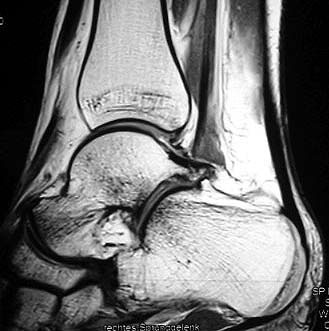

Z.n. Distorsion des Fußes mit „Ruptur“ der (vorbestehenden) talocalcanearen Coalitio. Die Wassereinlagerung in den an die Coalitio angrenzenden knöchernen Bezirken ist im MRT gut zu erkennen. Nach monatelangen Beschwerden spontane Besserung.

Abbildung 1

• Anhaltende Schmerzen nach vermeintlichen oder tatsächlichen Distorsionen („Aktivierung“ der Coalitio, vgl. Abb. 1)